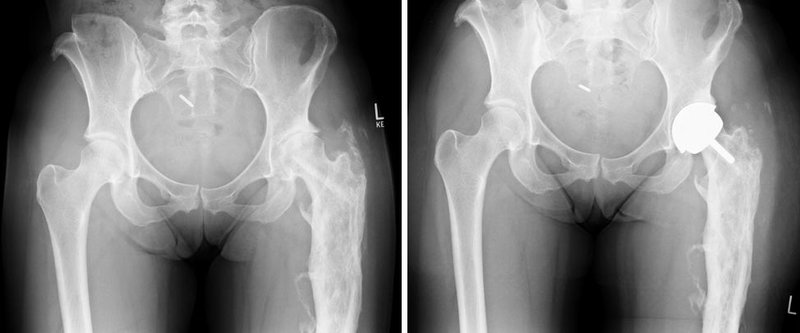

Die Patientin war aufgrund einer kindlichen Verletzung mit einer sogenannten Umstellungsoperation an der re. Hüfte voroperiert worden. Hierdurch lagen der gelenknahe Anteil des Oberschenkels sowie der Verlauf des Oberschenkelknochens nicht mehr in einer Achse. Eine herkömmliche Hüftendoprothese hätte nicht in den Oberschenkelschaft eingeführt werden können.

Die Patientin wurde mit einer modular zusammensetzbaren Spezialprothese versorgt und der alte Abstand zwischen Oberschenkelknochen und Becken konnte so wieder rekonstruiert werden (Abbildung 2).